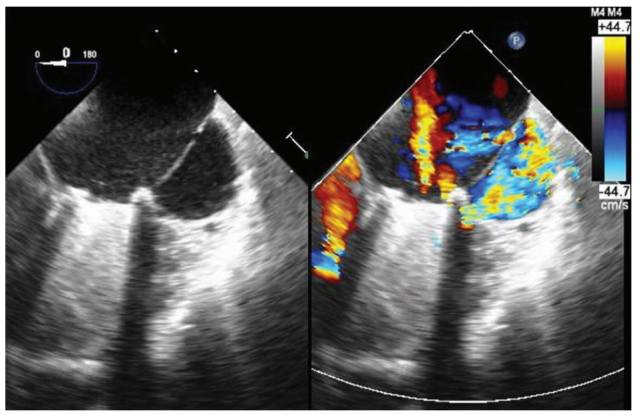

患者为 59 岁女性,因持续进展的呼吸困难和利尿剂治疗无效的下肢水肿而入院治疗,16 年前曾因风湿性做过二尖瓣置换手术和三尖瓣瓣环成形术(De Vega 法,非硬质环)。ECG 结果显示有房颤。经胸壁超声心动图结果显示严重的三尖瓣反流,保留左室和右室收缩性心功能,收缩期肺动脉压轻度升高,以及异常的室腔样结构。因此,经食管超声心动图(TE)结果如图 1 所示。

图 1 经食管超声心动图的四腔图。

问题:这种异常的室腔样结构是什么?

答案:C

食管裂孔疝,是由于食管与胃连接部位的错位导致部位胃进入了胸腔纵隔,在超声心动图上表现类似于心脏肿物。冠脉假瘤是部分冠脉异常扩张。在本例中,施加压力后出现瓣周血液漏入腔室,这个现象便可排除掉左心房肿物、心包积液、食管裂孔疝和冠脉假瘤。